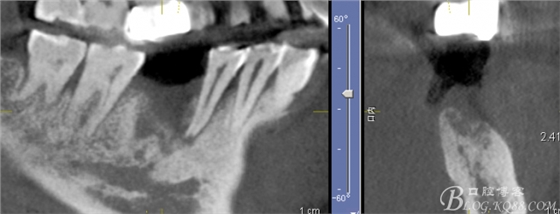

CT可見(jiàn)根管內(nèi)有白色顯影物和根周較大暗影

從根管影像看治療還是不錯(cuò)的,

懷疑牙根微裂,

所以建議患者手術(shù)探查